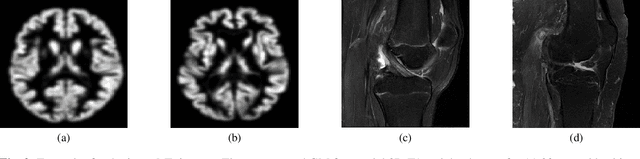

Abstract:Individuals age differently depending on a multitude of different factors such as lifestyle, medical history and genetics. Often, the global chronological age is not indicative of the true ageing process. An organ-based age estimation would yield a more accurate health state assessment. In this work, we propose a new deep learning architecture for organ-based age estimation based on magnetic resonance images (MRI). The proposed network is a 3D convolutional neural network (CNN) with increased depth and width made possible by the hybrid utilization of inception and fire modules. We apply the proposed framework for the tasks of brain and knee age estimation. Quantitative comparisons against concurrent MR-based regression networks illustrated the superior performance of the proposed work.